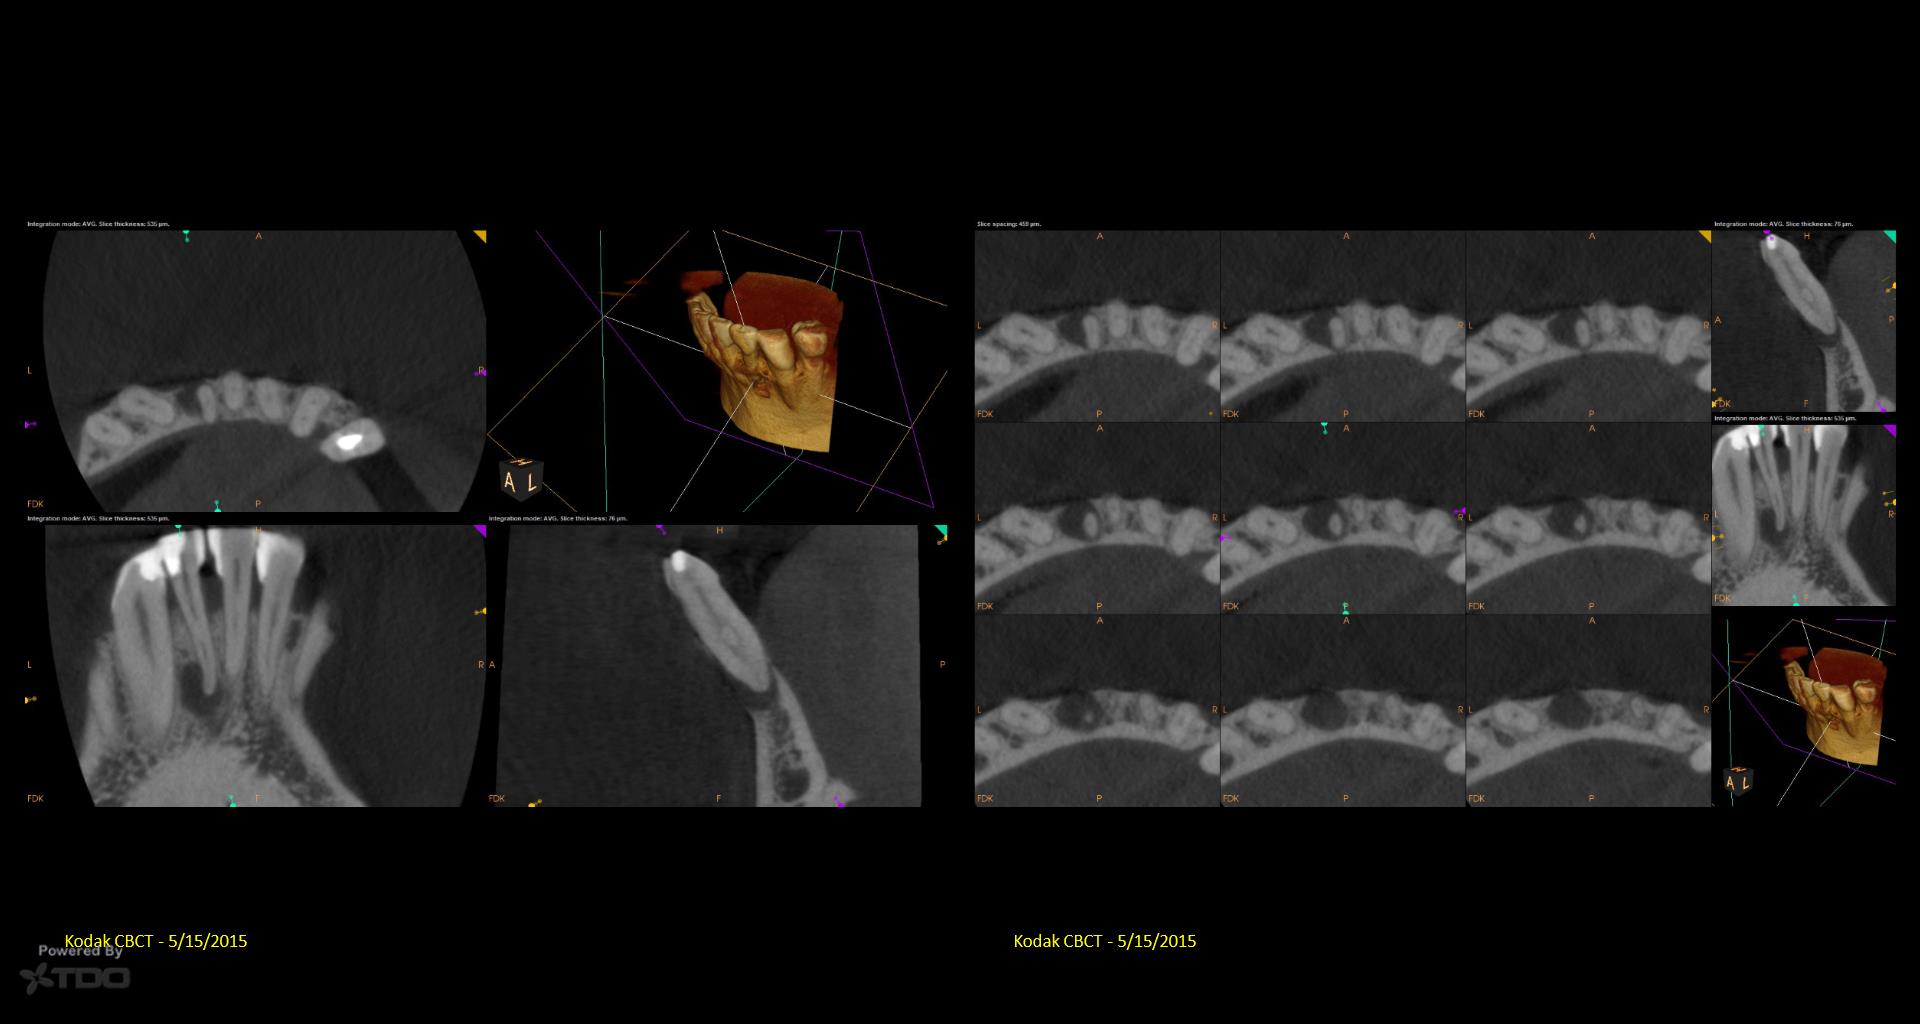

It’s a little embarrassing…but I have been treating a tooth of Joy’s for 5 years….Multiple CaOH visits over those 5 years. Coulod never get the area to resolve. Finally tried a GW on it…..1 yr recall today. gbc